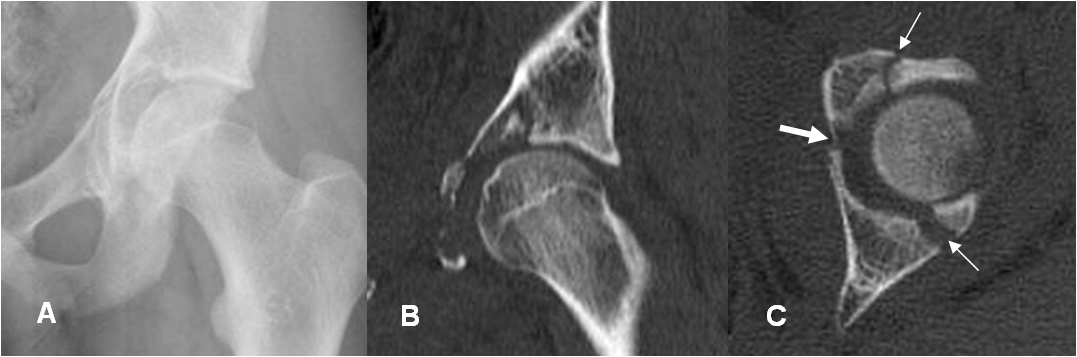

Fig 56. Fractura de acetábulo.

Rx AP. En el lado derecho hay fracturas oblicuas sobre el acetábulo (Flechas delgadas) y en el ramo iliopúbico. (Flecha gruesa). En la cadera izquierda no se aprecian alteraciones.

Fig 57. Fractura de acetábulo. Igual paciente anterior.

A: TAC reconstrucción coronal. Fractura oblicua, del techo acetabular.

B: TAC axial. Fractura en la parte anterior y posterior del techo acetabular.

C: TAC axial. Subluxación de la cabeza femoral, con fractura conminuta del reborde posterior.